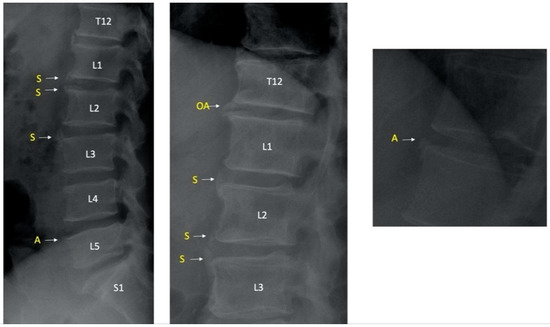

2.4. Pelvic and Lumbar X-ray Readings and Definitions

3.5. Ambiguous Lesions on Lateral Lumbar Radiograph in PsA Patients

3.6. AP Lumbar Radiographs in PsA Patients